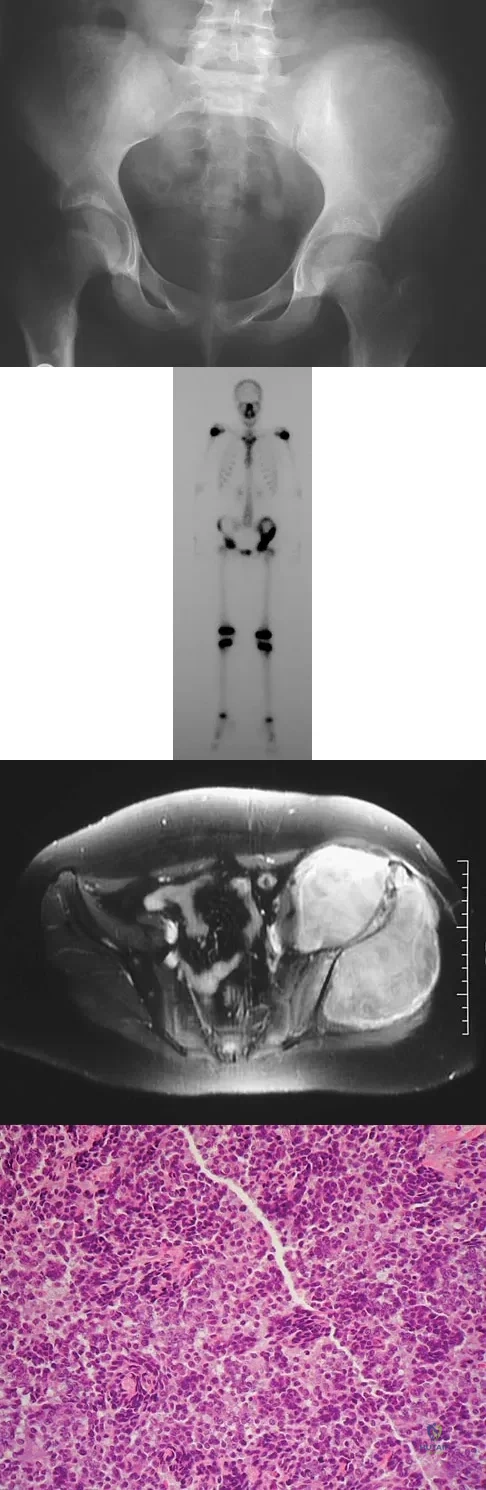

A 13-year-old girl has had increasing left hip pain for the past 4 months. A radiograph, bone scan, MRI scan, and photomicrograph are shown in Figures 1a through 1d. Which of the following immunohistochemistry results would confirm the most likely diagnosis?

Explanation